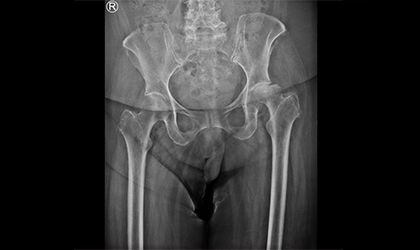

This 82-year-old lady, mother of a doctor, developed sudden and rapidly worsening hip pain over the course of a month. Initial concerns pointed to a possible infection due to the rapid collapse of the joint. Further evaluation confirmed a rare condition — rapidly progressive osteoarthritis, which is effectively treated with a single-stage hip replacement.We used a dual mobility here to reduce the risk of dislocation. She was in hospital for 3 days and is delighted with the results as she is pain free and back to normal mobility

Following a successful single-stage hip replacement using a dual mobility implant, the patient is now completely pain-free and mobile. She has returned to her normal routine with great satisfaction.